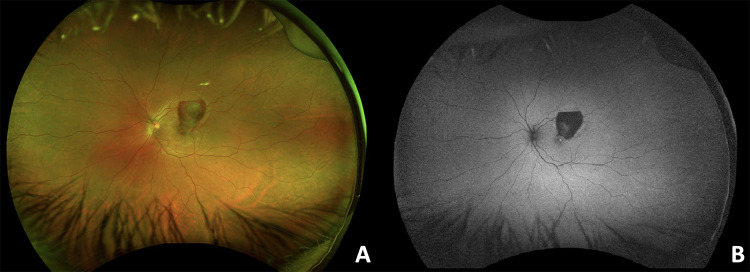

The current case report and literature review evaluate the management and optimal mode of delivery for Valsalva retinopathy in pregnancy. A 30-year-old primigravid female was discussed presenting with Valsalva retinopathy in the left eye at 35 weeks of gestation after dry heaving with a visual acuity of 20/200. Four weeks after cesarean-section, she had worse central vision and improving residual hemorrhage. A literature review of 25 Valsalva retinopathy cases showed all patients treated with laser posterior hyaloidotomy or pars plana vitrectomy achieved complete resolution (median of 1.5 weeks, p = 0.08), compared to 67% of untreated eyes (median of 5 months, p = 0.08). Average final visual acuity was 20/30 for the treated and untreated cohorts. Intervention may result in faster recovery time but with similar final visual acuity. Four (15%) cases of Valsalva retinopathy were incited by vaginal delivery. However, neither vaginal delivery nor cesarean section resulted in recurrence/worsening of premacular hemorrhage. These findings may help guide treatment of challenging Valsalva retinopathy cases in pregnancy.